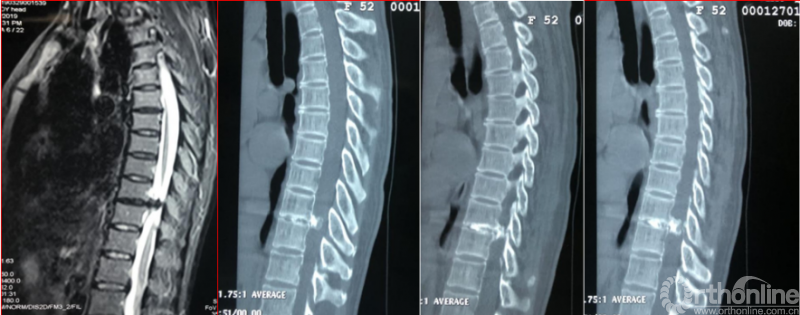

术后影像学资料

术后第二天资料

术后病情评估

术后第二天

JOA评分:8分;RR:37.5%(可);ASIA等级:D级。

术后8个月资料